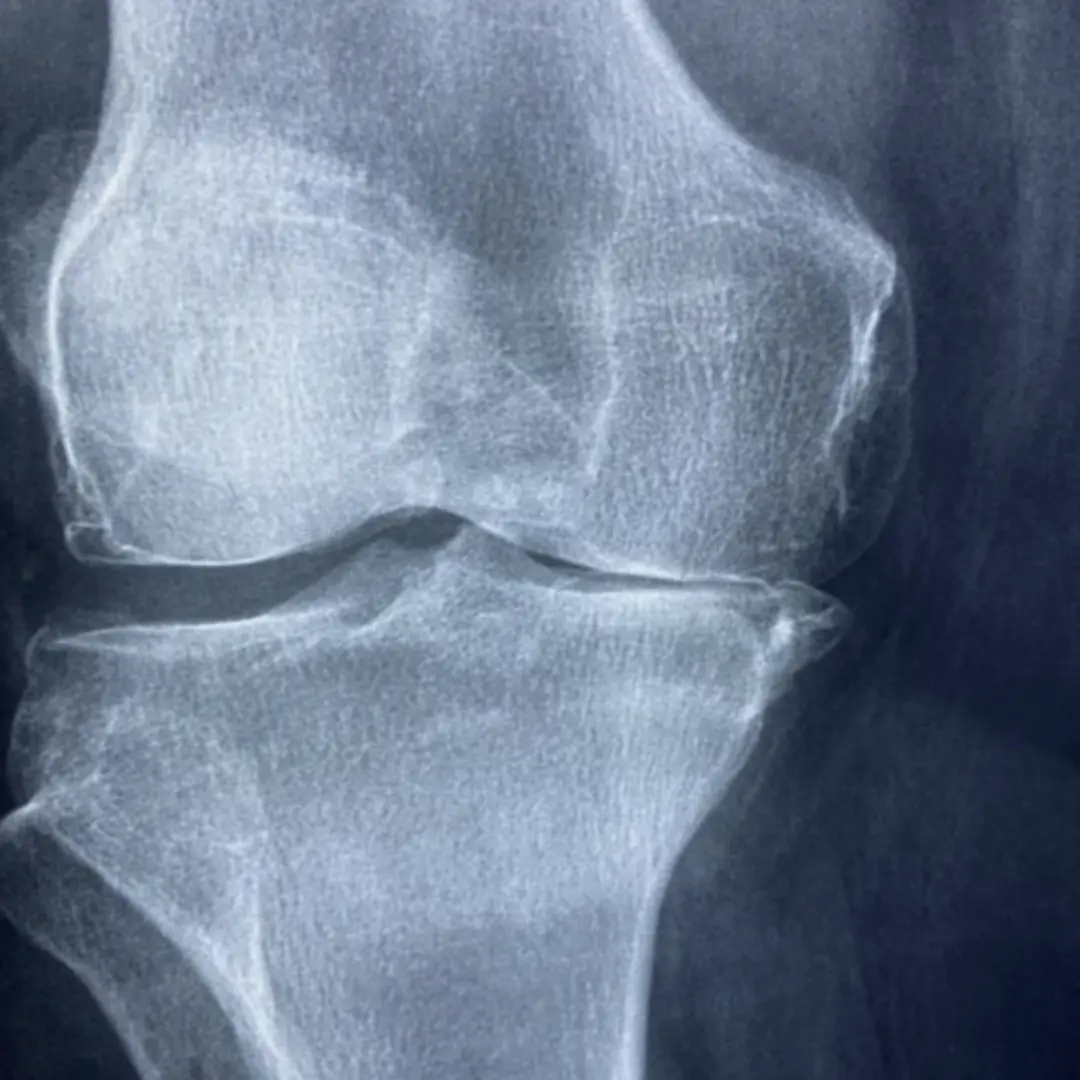

퇴행성 관절염은 가장 흔한 관절염으로, 주로 관절 연골의 손상으로 인해 발생해요. 초기증상은 연골이 닳기 시작하면서 나타난답니다.

- 외상 및 부상: 과거에 관절 부위를 다치거나 골절된 경험이 있는 경우, 해당 관절에 퇴행성 변화가 더 빨리 나타날 수 있답니다.